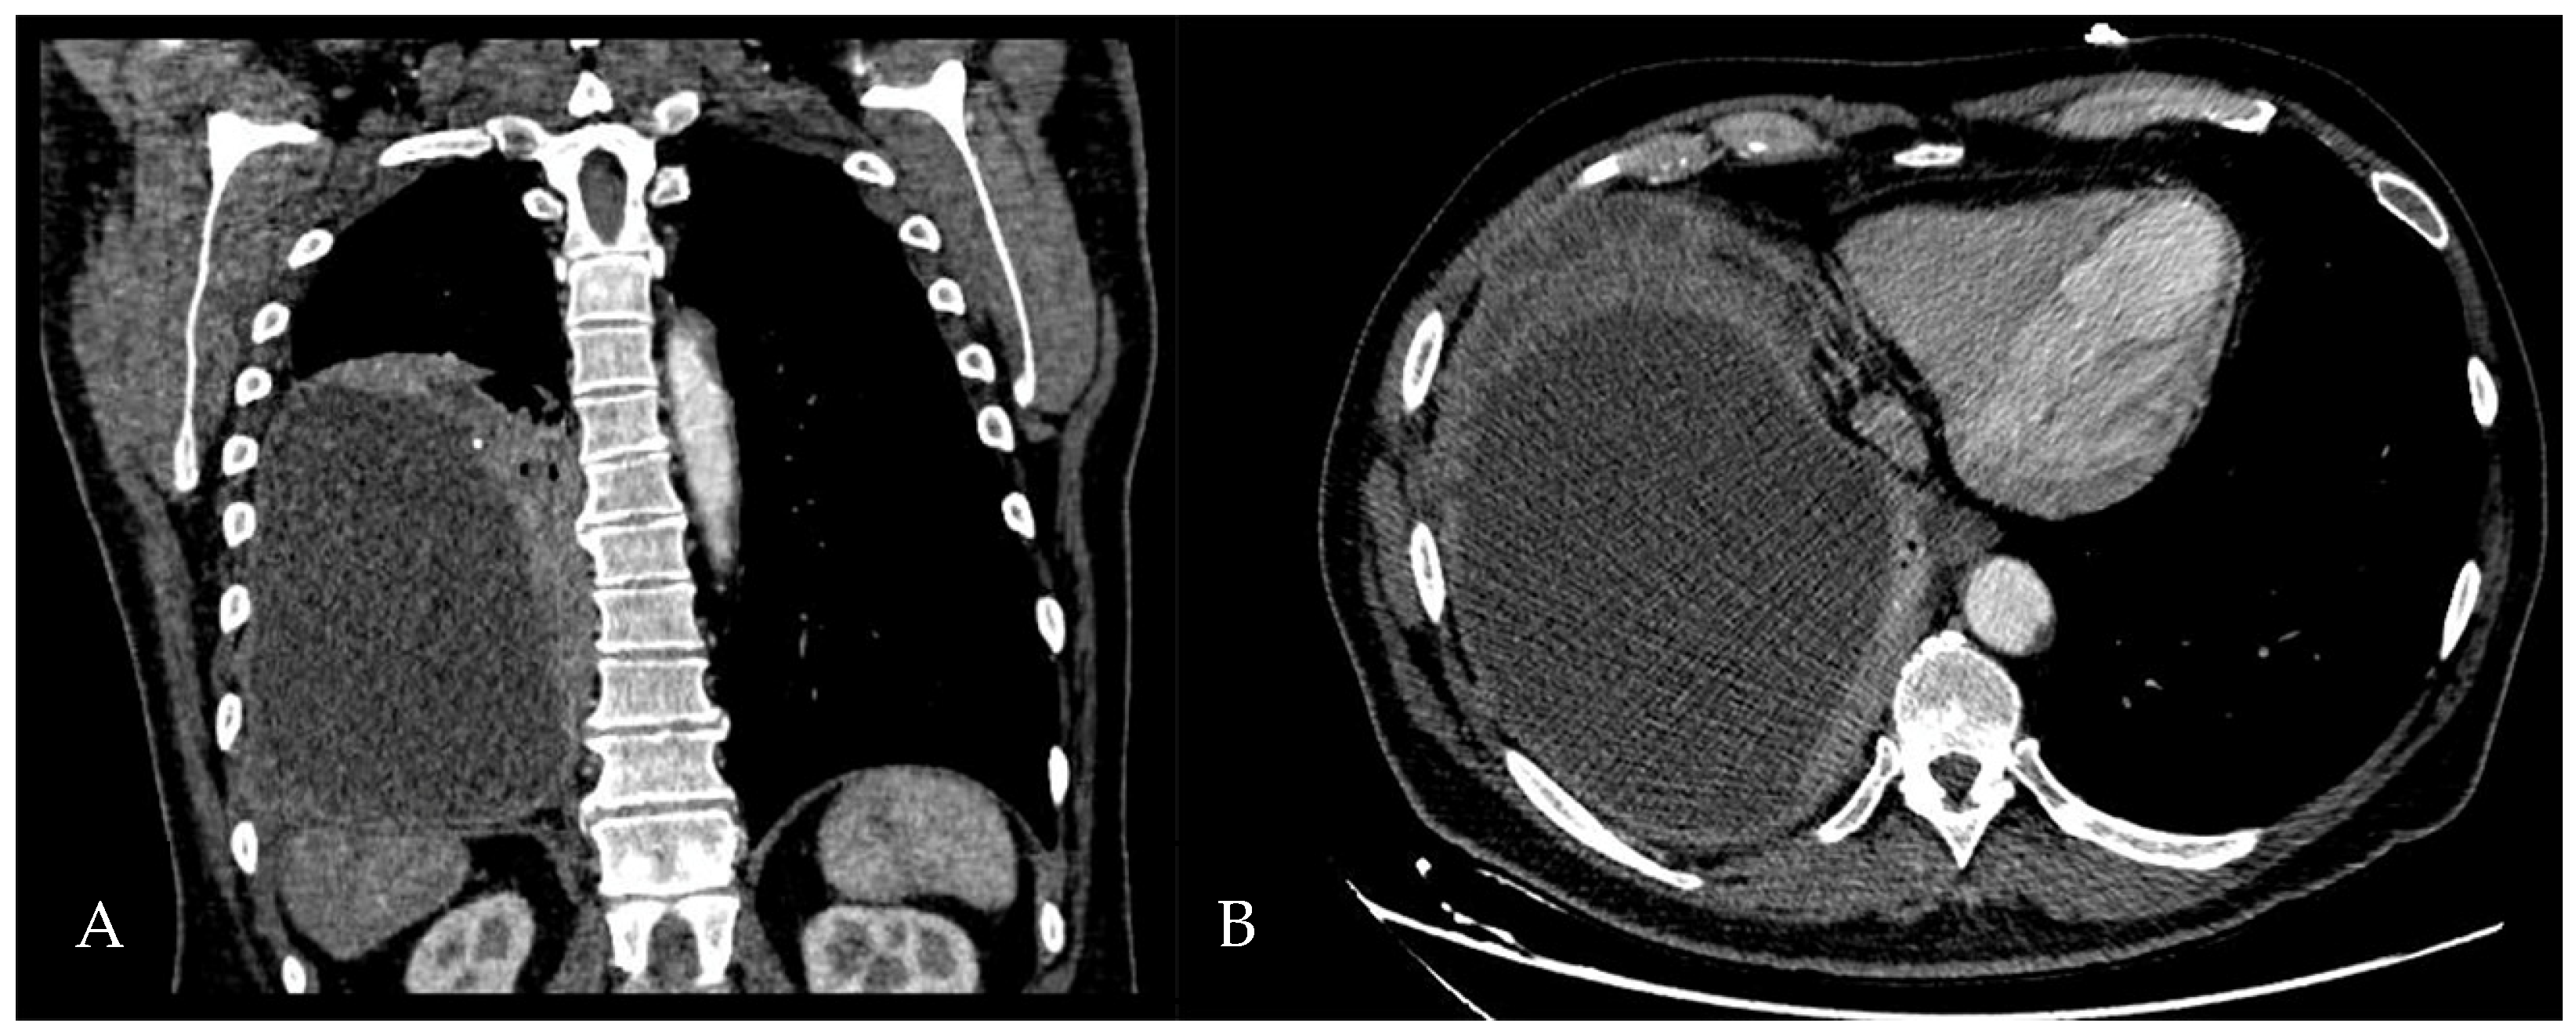

A 60-year-old Caucasian man was admitted to our hospital with a history of worsening pain at the base of the right hemithorax and feeling generally unwell for over one month. The patient’s past medical history included coronary heart disease, with a percutaneous coronary intervention in 2014. He smoked a half-pack of cigarettes per day for 40 years and had no history of respiratory disease. The CT chest scan showed a fluid collection in the medium–lower parts of the right hemithorax with thickened walls and contrast enhancement (Figure 5). This collection appeared in continuity with further smaller fluid collections with thickened walls, contrast enhancement, and confluence and caused the complete atelectasis of the middle and lower lobes and the partial atelectasis of the upper lobe, as well as middle and inferior lobar bronchus occlusion.

Figure 5. Chest CT scan of the mediastinal window in the coronal (A) and axial (B) plane, showing fluid collection in the medium–lower parts of the right hemithorax (maximum axial dimeters of 19 × 13 cm; craniocaudal extension of 16 cm) with thickened walls and contrast enhancement. There is also a complete atelectasis of middle and lower lobes and partial atelectasis of the upper lobe.